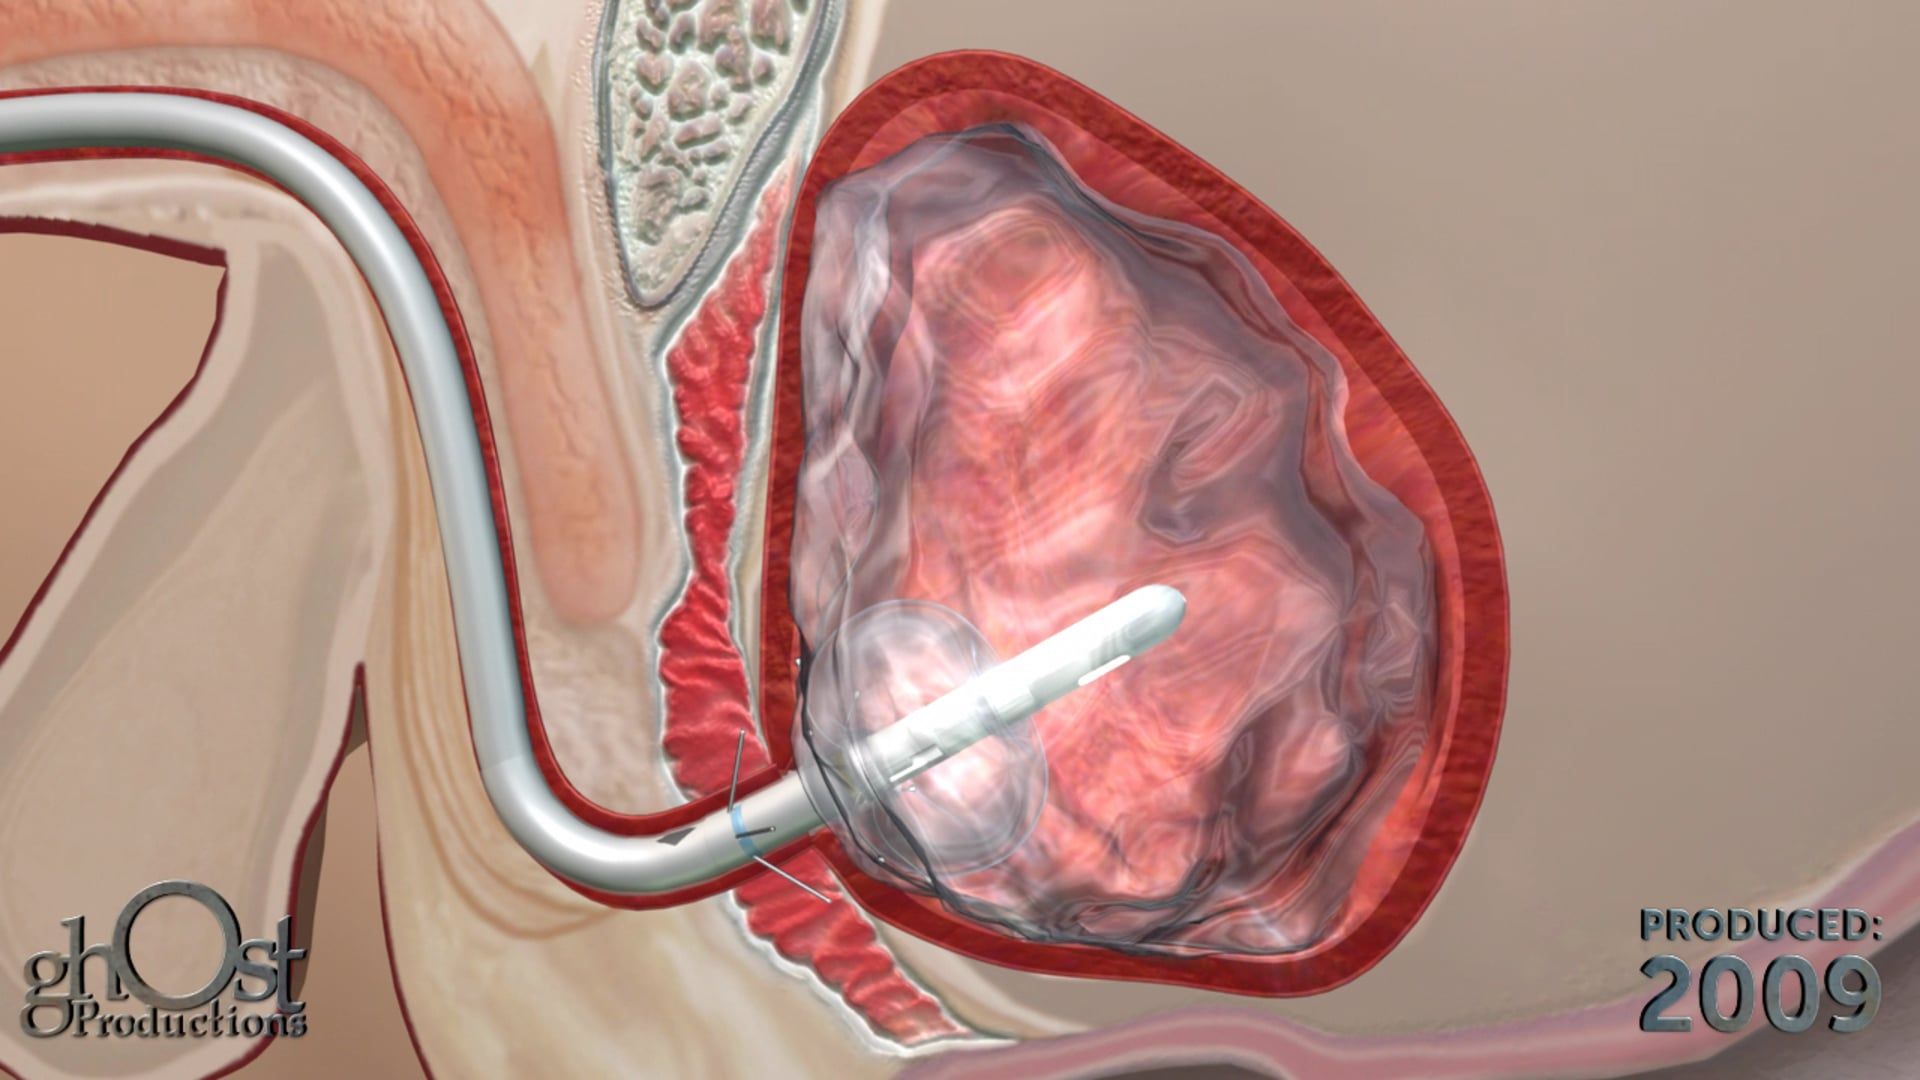

Discover the AMS Continuum, a reliable and innovative bladder anchored urinary catheter with retractable tines, through this stunning animation.

Looking for a reliable and effective bladder anchored urinary catheter with retractable tines? Look no further than the AMS Continuum, brought to life in stunning detail in this animation from Ghost Productions. Our team worked closely with American Medical Systems to create a visual representation of this innovative medical device, highlighting its unique features and benefits. Whether you're a healthcare provider looking for the latest in urinary catheter technology or a patient seeking a more comfortable and secure solution, the AMS Continuum is a game-changer. Watch our animation today to learn more!